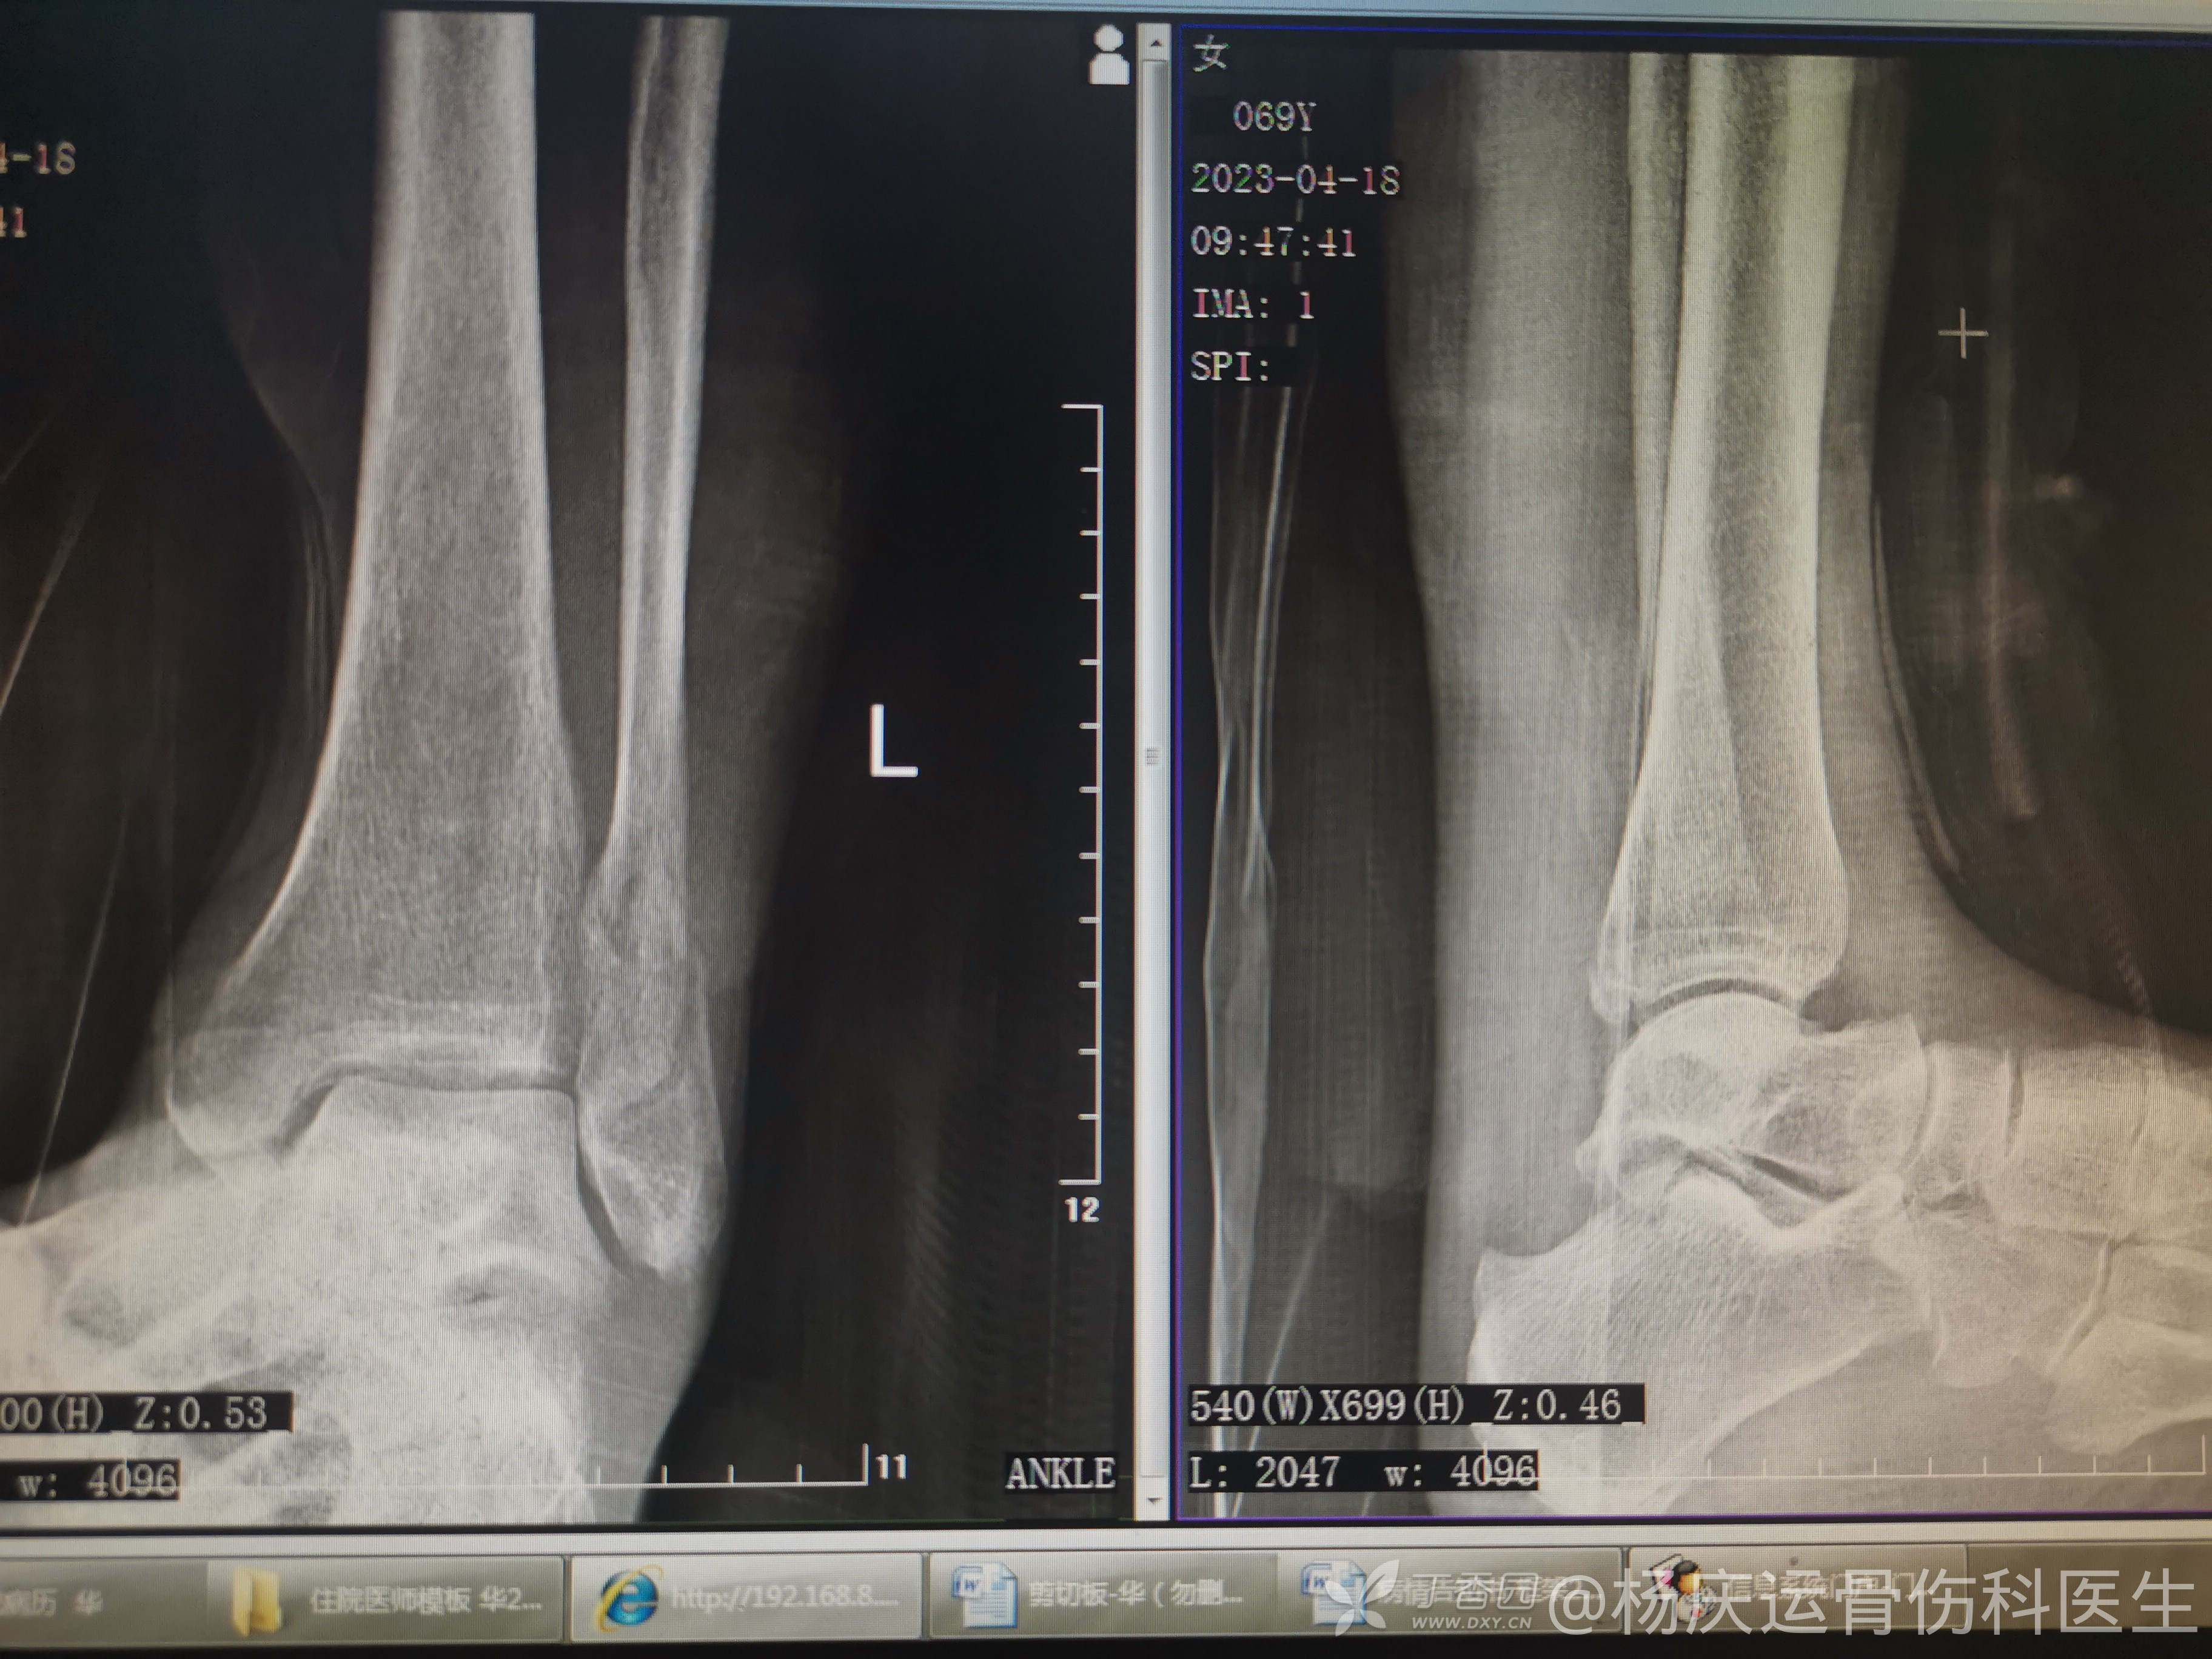

9天拍片